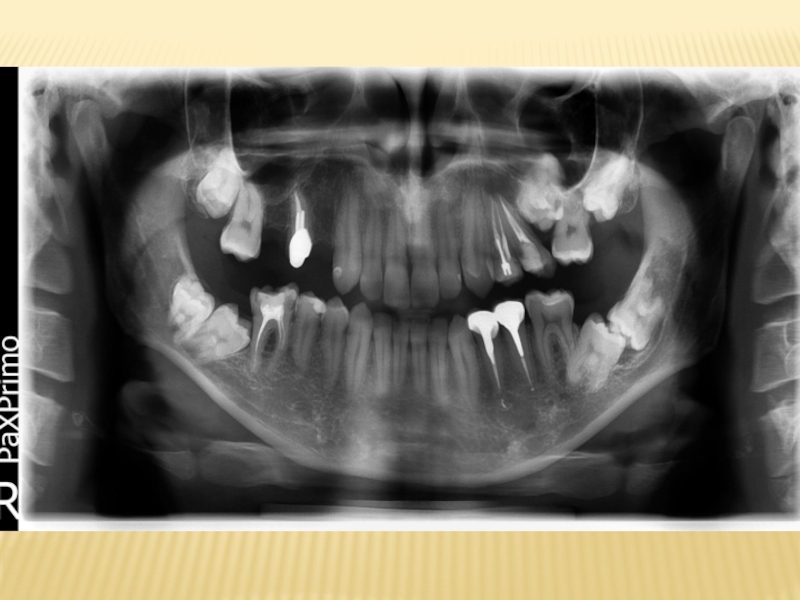

Для постановки диагноза и составления плана лечения используются следующие лучевые

методы исследования:

1) дентальная рентгенография

2) боковая рентгенография нижней челюсти

со стороны локализации патологического процесса;

3) ортопантомография

4) спиральная компьютерная томография;

5) конусно-лучевая компьютерная томография

Наиболее часто в практическом здравоохранении используются ден-тальная рентгенография и ортопантомография, однако оптимальными ме-тодами исследования при болезнях прорезывания являются ортопантомо-графия и конусно-лучевая компьютерная томография коническим пучком .

Эффективные дозы облучения при различных методах лучевой диагностики заболеваний челюстно-лицевой области следующие:

‒ при дентальной рентгенографии — 0,01–0,02;

‒ ортопантомографии — 0,07–0,15;

‒ спиральной компьютерной томографии с 3D-реконструкцией — 1,2–2,3;

‒ конусно-лучевой компьютерной томографии — 0,036